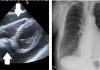

3. Pnömoni (zatürre)

-

Özellikle ağır seyirli nekrotizan pnömoni yapabilir

Yüksek ateş, hemoptizi, şok ve lökopeni görülebilir

Hastane ve ventilatör ilişkili pnömonide de önemli bir etkendir

5. Endokardit

Akciğerde septik emboliler görülebilir